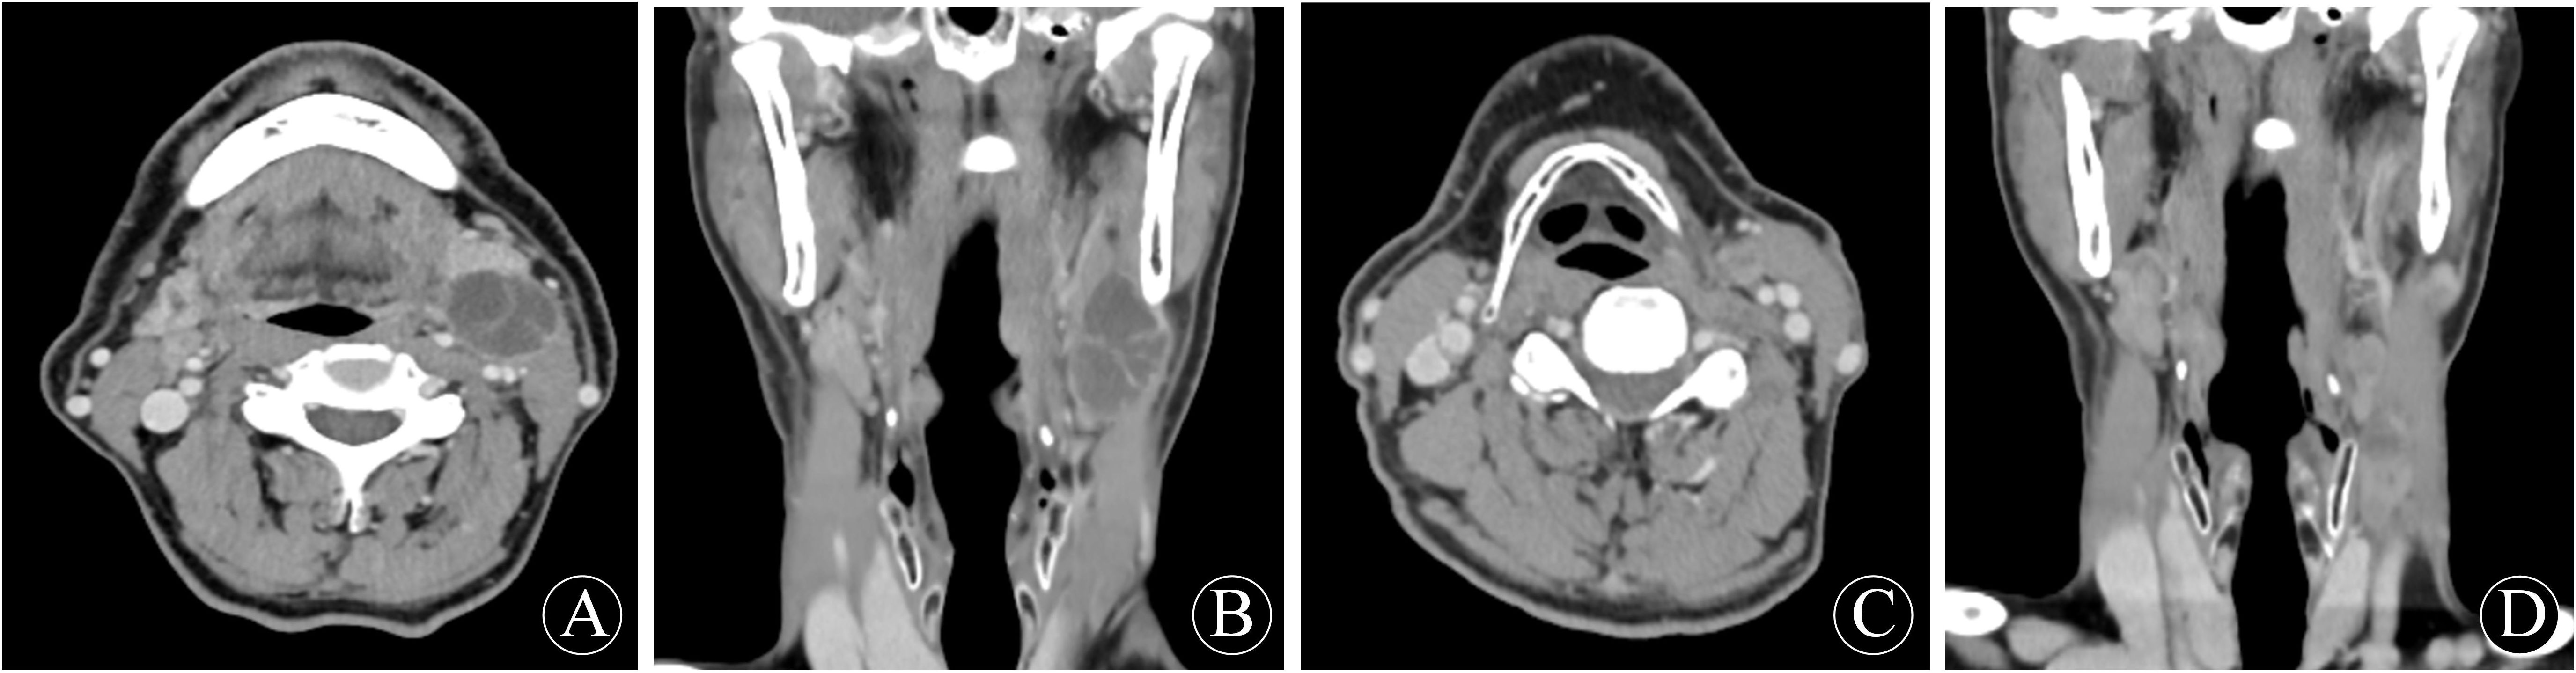

On 21 January 2025, the patient was readmitted to the hospital with a left cervical mass that had been present for more than 20 days. He complained of a left-sided neck swelling found after an upper respiratory tract infection more than 20 days ago. Accompanied by fever, sore throat, neck swelling, and pain, no symptoms such as limited neck movement, choking on food, or dyspnea. He was treated with antibiotics on his own, but the swelling did not subside. Physical examination: a round-like mass was palpated at the anterior border of the lower middle part of the left sternocleidomastoid muscle, about 3.0 cm×1.5 cm in size, tough, with poorly defined borders, with acceptable mobility and mild pressure pain. Enhanced CT of the neck showed multiple round-like nodules at the anterior and medial border of the left sternocleidomastoid muscle, about 3.1×1.5×1.2cm in size, and the enhanced lesions showed obvious uneven enhancement, which was considered to be enlarged lymph nodes in the left cervical level II and III. No significant lymph node enlargement was observed in the right neck. No significant space-occupying lesions were identified in the nasopharynx, oropharynx, hypopharynx, or parapharyngeal spaces. No abnormalities were noted in the thyroid, parotid, or submandibular glands. Electronic nasopharyngeal laryngoscopy and chest CT revealed no significant abnormalities. According to the previous history of malignant cyst of the left neck branchial cleft, metastatic lymph node cancer from branchial cleft carcinoma could not be excluded. After perfect preoperative preparation, left elective cervical lymph node dissection (level II-V) was performed under general anesthesia. During the operation, several enlarged lymph nodes were found, which were mainly located in the left cervical levels II and III. One of the larger lymph nodes in level II was partially adherent to the inferior border of the parotid gland. A tough lymph node of about 3.0×1.5 cm in level III was adherent to the internal jugular vein. In the fatty tissue between the left sternocleidomastoid muscle and the platysma muscle, there were two tough lymph nodes with a diameter of about 0.5 cm, which were recorded as superficial cervical lymph nodes. Postoperative pathology showed: metastatic carcinoma in lymph nodes (10/25), including level II (3/8), level III (3/7), level IV (2/7), level V (0/1), and the superficial cervical region (2/2). Immunohistochemistry: CKAE1/AE3: (+); CK5/6: (+); P63: (+); Vimentin (-); P16: (-); CK7: (-); Ki-67: (+) S was 60%. The diagnosis of branchial cleft carcinoma with cervical lymph node metastasis was made based on two pathological and immunohistochemical findings and history. The patient did not experience any postoperative complications corresponding to vascular or nerve injury. Four weeks after surgery, following the recommendation of the MDT committee, the patient underwent adjuvant radiotherapy (covering the left neck II-V regions and Waldeyer’s ring area, with a total dose of 60 Gy in 30 fractions). On review 4 months after surgery, no tumor recurrence, metastasis, or other primary cancers were seen on systemic examination. The examination results are shown in Figure 1 and Figure 2.

Figure 1

First preoperative neck enhancement CT performance: (A) transverse position; (B) coronal position. Second preoperative neck enhancement CT performance: (C) transverse position; (D) coronal position.